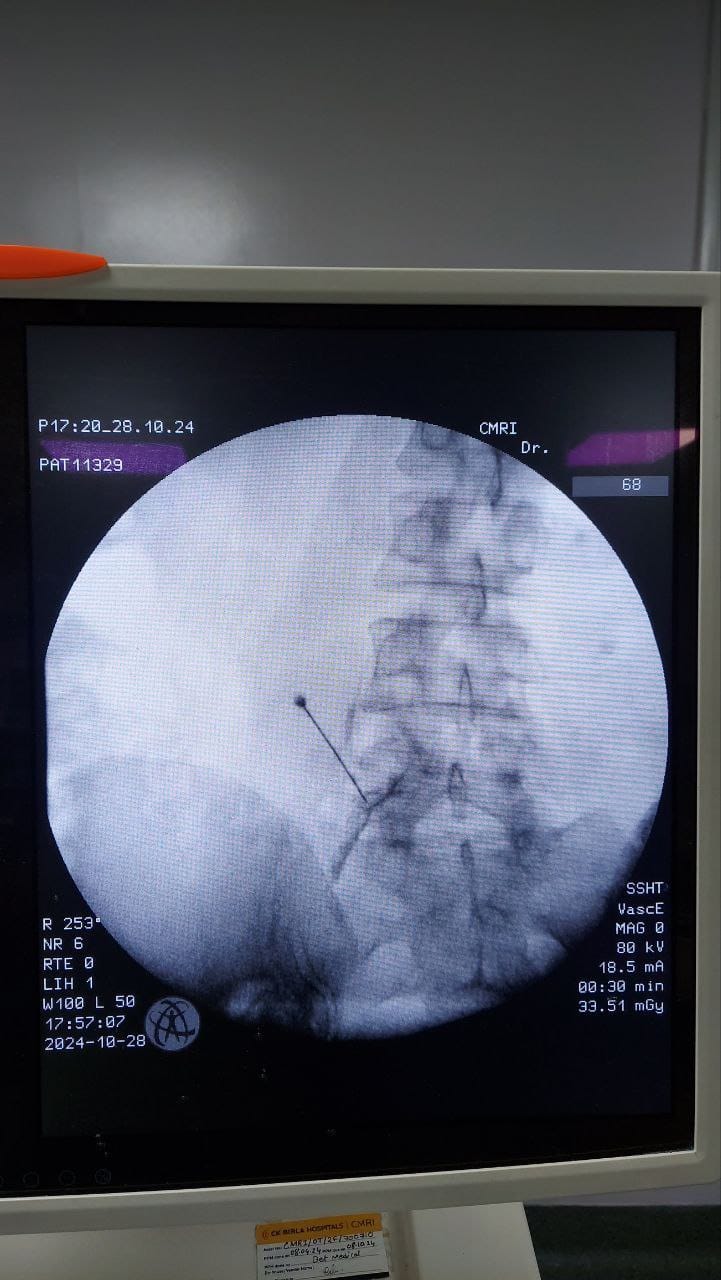

Procedures